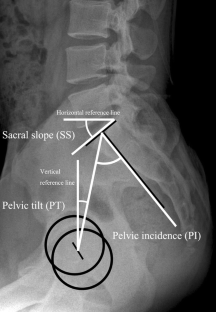

From March 2010 to May 2012, 240 consecutive patients with painful vertebral compression fractures (VCFs) were enrolled in a retrospective study. Ninety-one patients with VCFs underwent percutaneous vertebroplasty (VP) at 112 levels. The sagittal vertical axis (SVA), thoracic kyphosis (TK), lumbar lordosis (LL), sacral slope (SS), pelvic tilt (PT), pelvic incidence (PI), and segmental kyphotic angle on sagittal standing radiographs were used to evaluate radiologic outcomes.

In 2 years, 15 out of 134 patients (11.1 %) treated with conservative treatment, and 12 out of 91 patients (13.1 %) treated with VP sustained adjacent level fracture. More patients with the BMD higher or equal to 3.0 experienced a new fracture than those with a BMD less than 3.0 (p = 0.019), and the risk for adjacent level fractures decreased significantly when segmental kyphotic angle was less than 11° (p = 0.001), SVA was less than 6 cm (p = 0.001), SS was higher or equal to 25° (p = 0.004), and LL was higher or equal to 25° (p = 0.020).

The most important factors for new VCFs after the initial compression fractures are the degree of osteoporosis and altered biomechanics due to the spinopelvic imbalance in the fractured area of the spine. Regarding the spinopelvic alignment to investigate the relationship with a subsequent AVF, segmental kyphotic angle, SS, LL, and SVA may be a potential predictor.